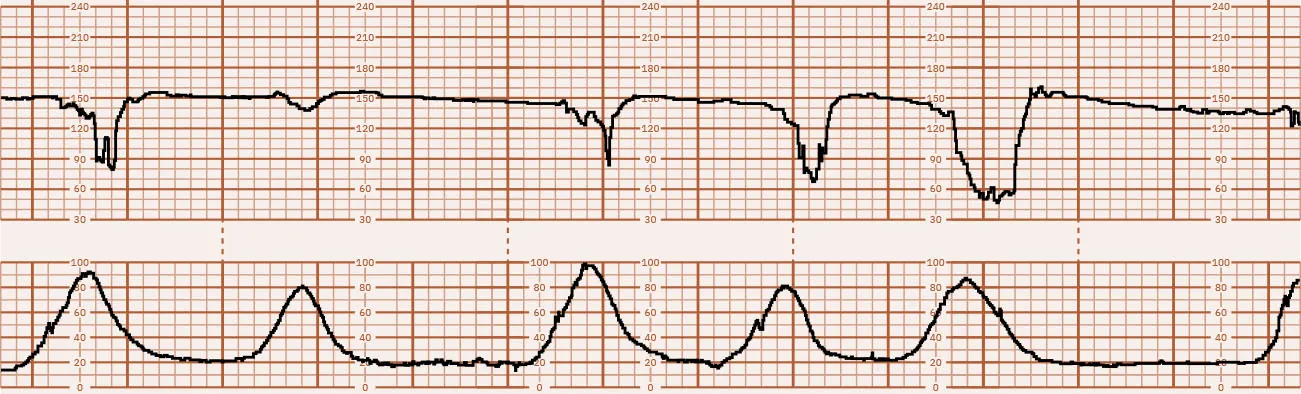

Fetal well-being is influenced by uterine activity. Therefore, when the nurse is evaluating fetal well-being, both the fetal heart rate and uterine activity, as well as the fetal response to the uterine activity, must be described. A normal fetal monitor tracing is found in Figure 16.24.

Category I tracings are considered normal and do not require further actions by the nurse other than routine nursing care for the antepartum or laboring patient. Figure 16.26 shows a Category I tracing. Category II tracing characteristics do not meet the criteria of either Category I or III. Nursing care requires continued surveillance with consideration of clinical circumstances and reevaluation and notification of the health-care provider. Figure 16.27 shows a Category II tracing. Category III tracings are always considered abnormal and require the nurse to contact the health-care provider with a report of the FHR abnormalities. Nursing interventions aimed at resolving the cause of the abnormality are discussed in 16.5 Intrauterine Resuscitation in this chapter. If interventions do not resolve the abnormality, the birth must be expedited, most commonly via cesarean section (ACOG, 2009). Figure 16.28 shows a Category III tracing.

Fetal heart rate reading showing accelerations, moderate variability, no decelerations, and uterine contractions suggesting early labor.

Figure 16.26 Category I Fetal Heart Rate Tracing This fetal heart rate tracing shows accelerations, moderate variability, no decelerations, and uterine contractions suggesting early labor. (attribution: Copyright Rice University, OpenStax, under CC BY 4.0 license)